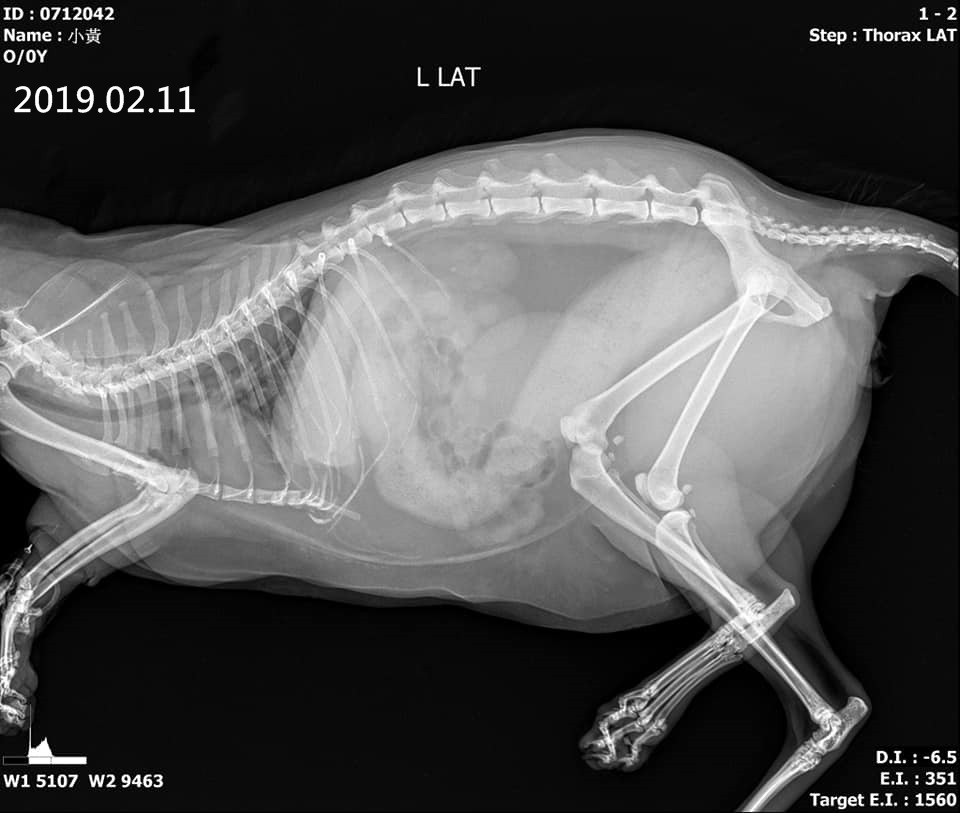

主題: 巨結腸排便困難的三腳小黃 申請者姓名: 臺北市支持流浪貓絕育計劃協會 花色: 申請日期: 2019-03-01 19:35:28 申請者部落格: 申請者臉書網址: http://www.tnrtw.org/ 所在縣市/合作醫院: 台北市/沐恩動物醫院 治療費用: 20600元 需求人數: 45人 已結案 (2024-05-31 18:34:18) 報名人員: chiawei(已付款)、Mia Jheng(已付款)、左凱騏(已付款)、Angel Lin(已付款)、黃琦珊(已付款)、Irene(已付款)、鬼如來(已付款)、平(已付款)、olivia_491025 x4(已付款)、簡佑銘(已付款)、Bex Chao(已付款)、蟲(已付款)、魚仔(已付款)、yangmimi x2(已付款)、巨結腸排便困難的三花小黃、香菇(已付款)、長春路四面佛(已付款)、sandy_huanglichuan、Amber Chen(已付款)、瓦莉阿嬤(已付款)、sbjenny x2(已付款)、amberkuyin(已付款)、陳昱先 x2(已付款)、Avis(已付款)、Yt(已付款)、Moon x4(已付款)、Yen Yen(已付款)、Gia Hung(已付款)、黃小金(已付款)、黃吉兒(已付款)、小珍 x2(已付款)、Candace Shiue x2(已付款)、簡阿喵(已付款)、可樂 x3(已付款)、 候補人員: 動物病情說明: 小黃是103年間被協會救援的貓咪,他原本在台南某戶人家的後院生活,那戶好心人家會餵食小黃,一日發現小黃的前肢長了一顆腫瘤,幾個月下來腫瘤越來越大,這戶人家無法捉到小黃帶他就醫,於是向外求助,志工們自台北去到台南誘捕到小黃並送往重症醫院治療。

小黃因非常瘦弱,住院觀察了幾天才進行手術將腫瘤取出,但因腫瘤過大,無奈需一併截肢,先前的流浪生活及腫瘤讓小黃的健康情況很不好,腸道結構改變、大腸太粗、有巨結腸,致大便容易累積排不出,所以小黃需要長期吃軟便劑等藥物以幫助排便,並須定期回診追蹤檢查。

2018年12月間,照護員發現小黃食慾降低,精神不好、嘔吐,還有出現泥便情形,因此於12月20日約診至沐恩醫院進行檢查,血檢結果與前次相比是有些進步、沒有胰臟炎,但磷指數下降許多醫師研判應與泥便有關,先繼續服藥、打皮下輸液、仔細觀察並持續回診;至12月底,小黃的磷指數有進步,但2019年1月28日小黃開始出現水便、並久蹲無便因而就醫,先讓小黃吃杜化液、腸蠕動劑看可否改善,2月9日小黃再度出現排便困難情況,照護員摸到肛門附近有一塊大便,但無法協助排出,所以再至沐恩就診,醫師把最外部的乾硬大便挖出,有觸診到有一截較硬的大便,但因離肛門口還有段距離,加上小黃腹部脂肪較厚無法徒手將糞便往後推,所以無法挖出,先增加皮下注射液,改為早晚各100cc的乳酸林格、早晚皆吃軟便劑、3cc杜化液治療,但排便情況仍不夠理想,於是在2月11日進行麻醉挖便,醫師囑咐術後持續用藥、皮下輸液及多給小黃喝水。

小黃的排便問題會須要長期的醫療,本筆醫助是小黃在沐恩醫院自2018年12月20日至2019年2月11日的醫療費用,包含血檢、用藥、X光、灌腸等,請大家一起幫忙小黃,謝謝。

2019-02-11

小黃 沐恩就診 楊醫師

體重:5.87Kg

一、就診狀況:

血檢都還不錯,腎指數有下降一點,可能皮下注射水分較充足,白血球有上升一點,可能跟便祕狀況有關。